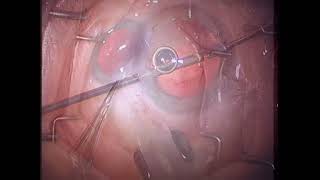

Anterior Vitrectomy Tips video

Anterior Vitrectomy Technique for Cataract Surgeons. The Answers all surgeons should know: Dr Megur

Anterior Vitrectomy Technique for Cataract Surgeons. The Answers all surgeons should know: Dr Megur Anterior Vitrectomy Tips

Anterior Vitrectomy Tips 186 10 tips for anterior vitrectomy by Dr Nidhi Patwardhan

186 10 tips for anterior vitrectomy by Dr Nidhi Patwardhan Principles of performing 'Anterior vitrectomy' - surgical tips and nuances.

Principles of performing 'Anterior vitrectomy' - surgical tips and nuances. CataractCoach™1805: curriculum lesson 21: anterior vitrectomy